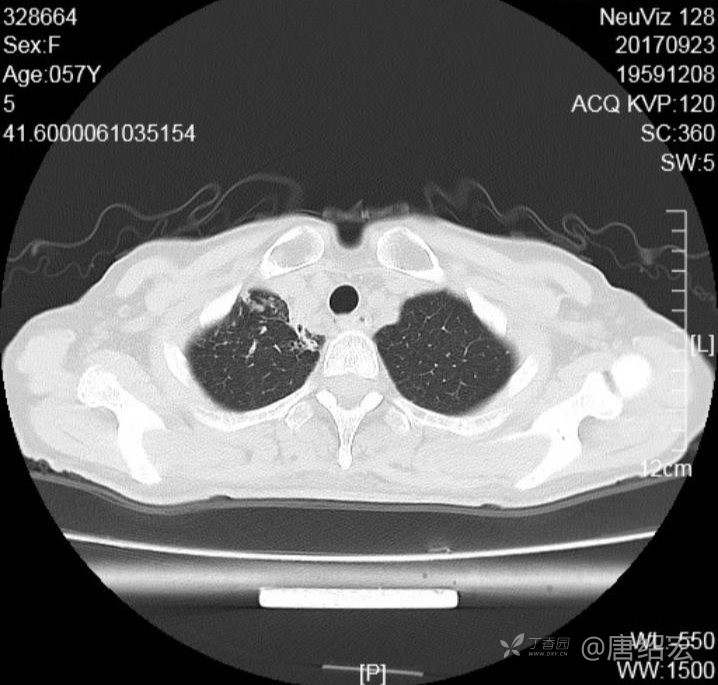

中年女性满肺树芽征还有支气管扩张,考虑什么疾病?

女,57岁,

主诉:发热、咳嗽、咯黄痰,胸闷3天入院。